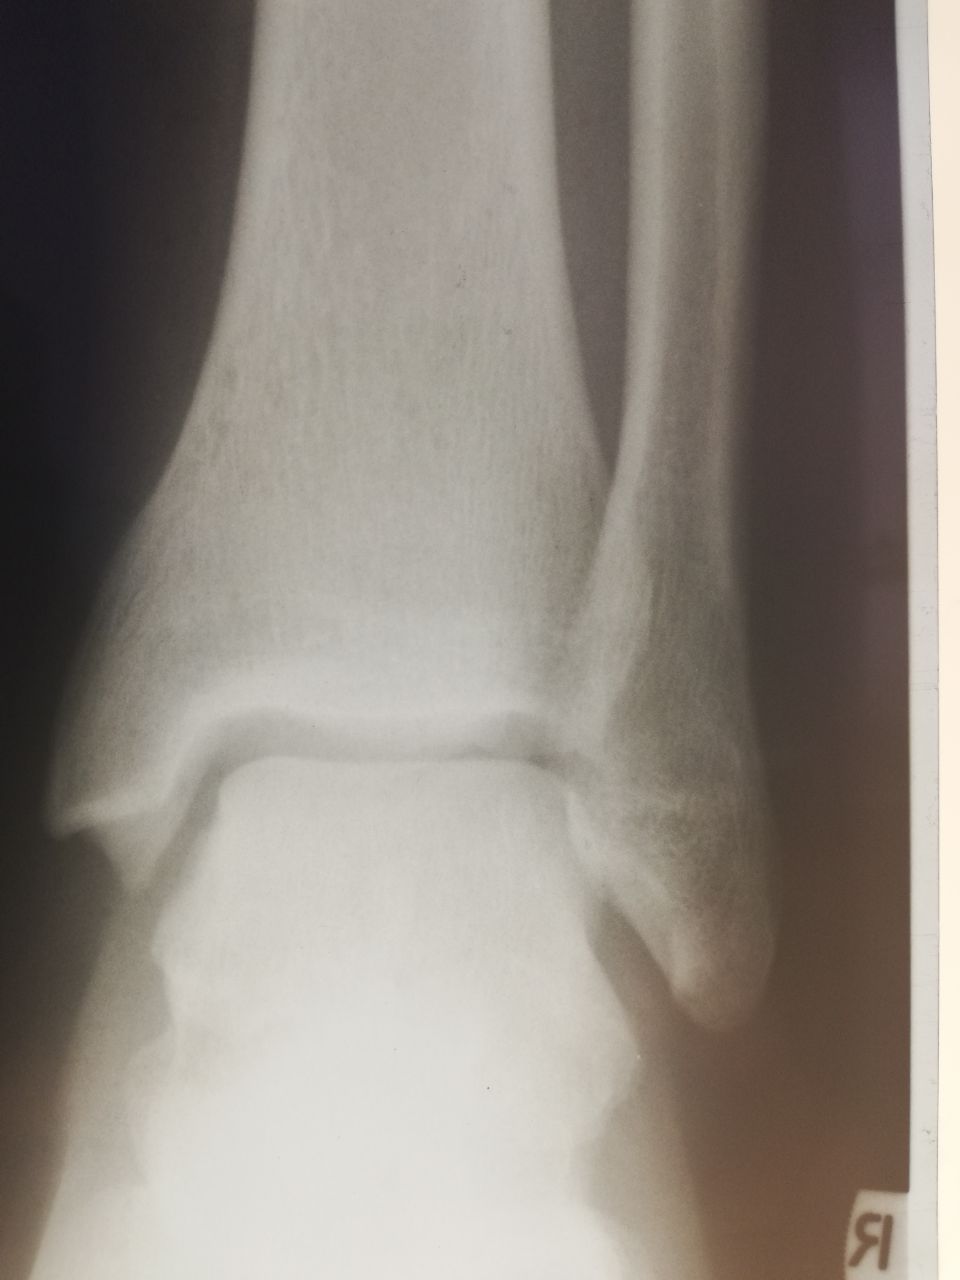

Здравствуйте! Мужчина, 37 лет, 3-4 недели назад была травма. Смущает отмеченный участок на латеральной лодыжке. Как думаете, есть ли перелом? И если есть, можно ли сказать о его консолидации?